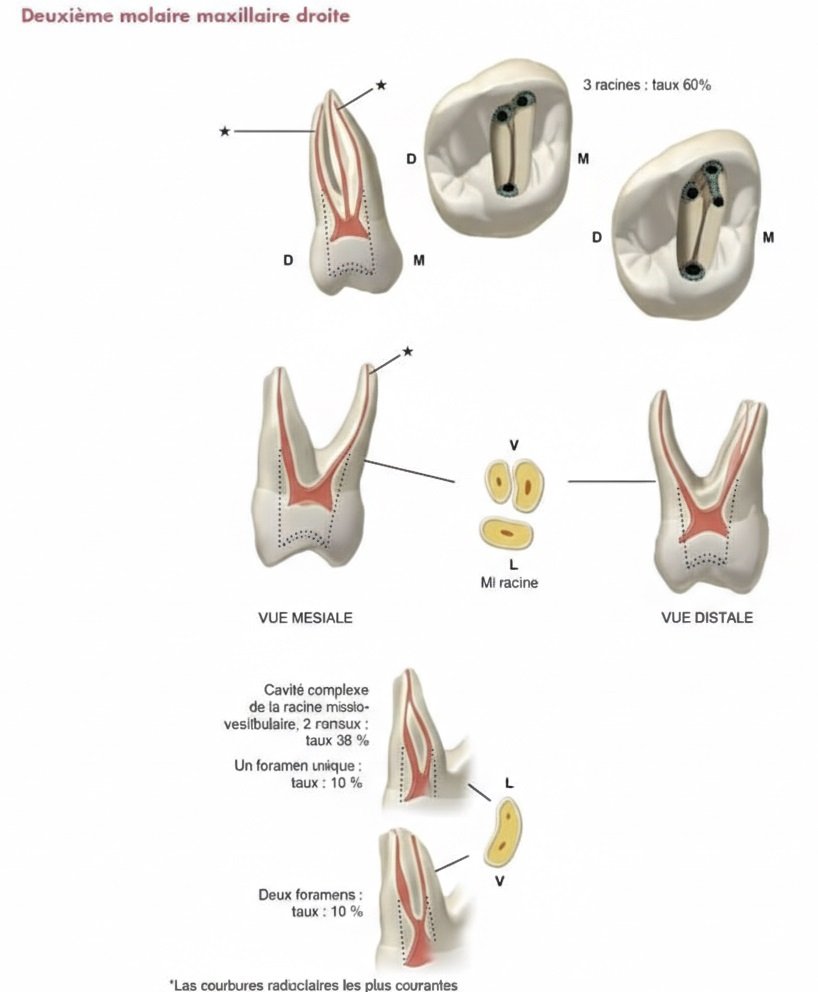

Deuxième et Troisième Molaires Maxillaires

Simplification : l’anatomie tend à se simplifier avec les molaires distales

MB2 : présent dans environ 60% des deuxièmes molaires (contre 90% pour les premières)

Alignement : les trois canaux tendent à s’aligner sur un même axe, facilitant le travail